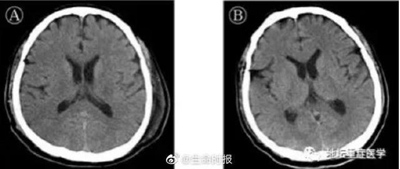

5 марта, ?Жэньминь жибао? онлайн -- По сообщению больницы Пекина ?Дитань? от 4 марта, 25 февраля из медучреждения был выписан пациент, которого вылечили от вызываемой коронавирусом нового типа пневмонии и энцефалита. Заведующий отделением интенсивной терапии больницы Лю Цзин отметил, что у больного было выявлено расстройство сознания.

По его словам, необходимо учитывать, что вирус, возможно, может поражать центральную нервную систему человека. Раннее было известно, что новая коронавирусная пневмония может стать причиной острого респираторного дистресс-синдрома, привести к травме миокарда, дисфункциям кровеносной системы, повреждению почек, печени и других органов, однако случаев поражения коронавирусом центральной нервной системы не было, это первый случай в истории мировой медицины. -о-